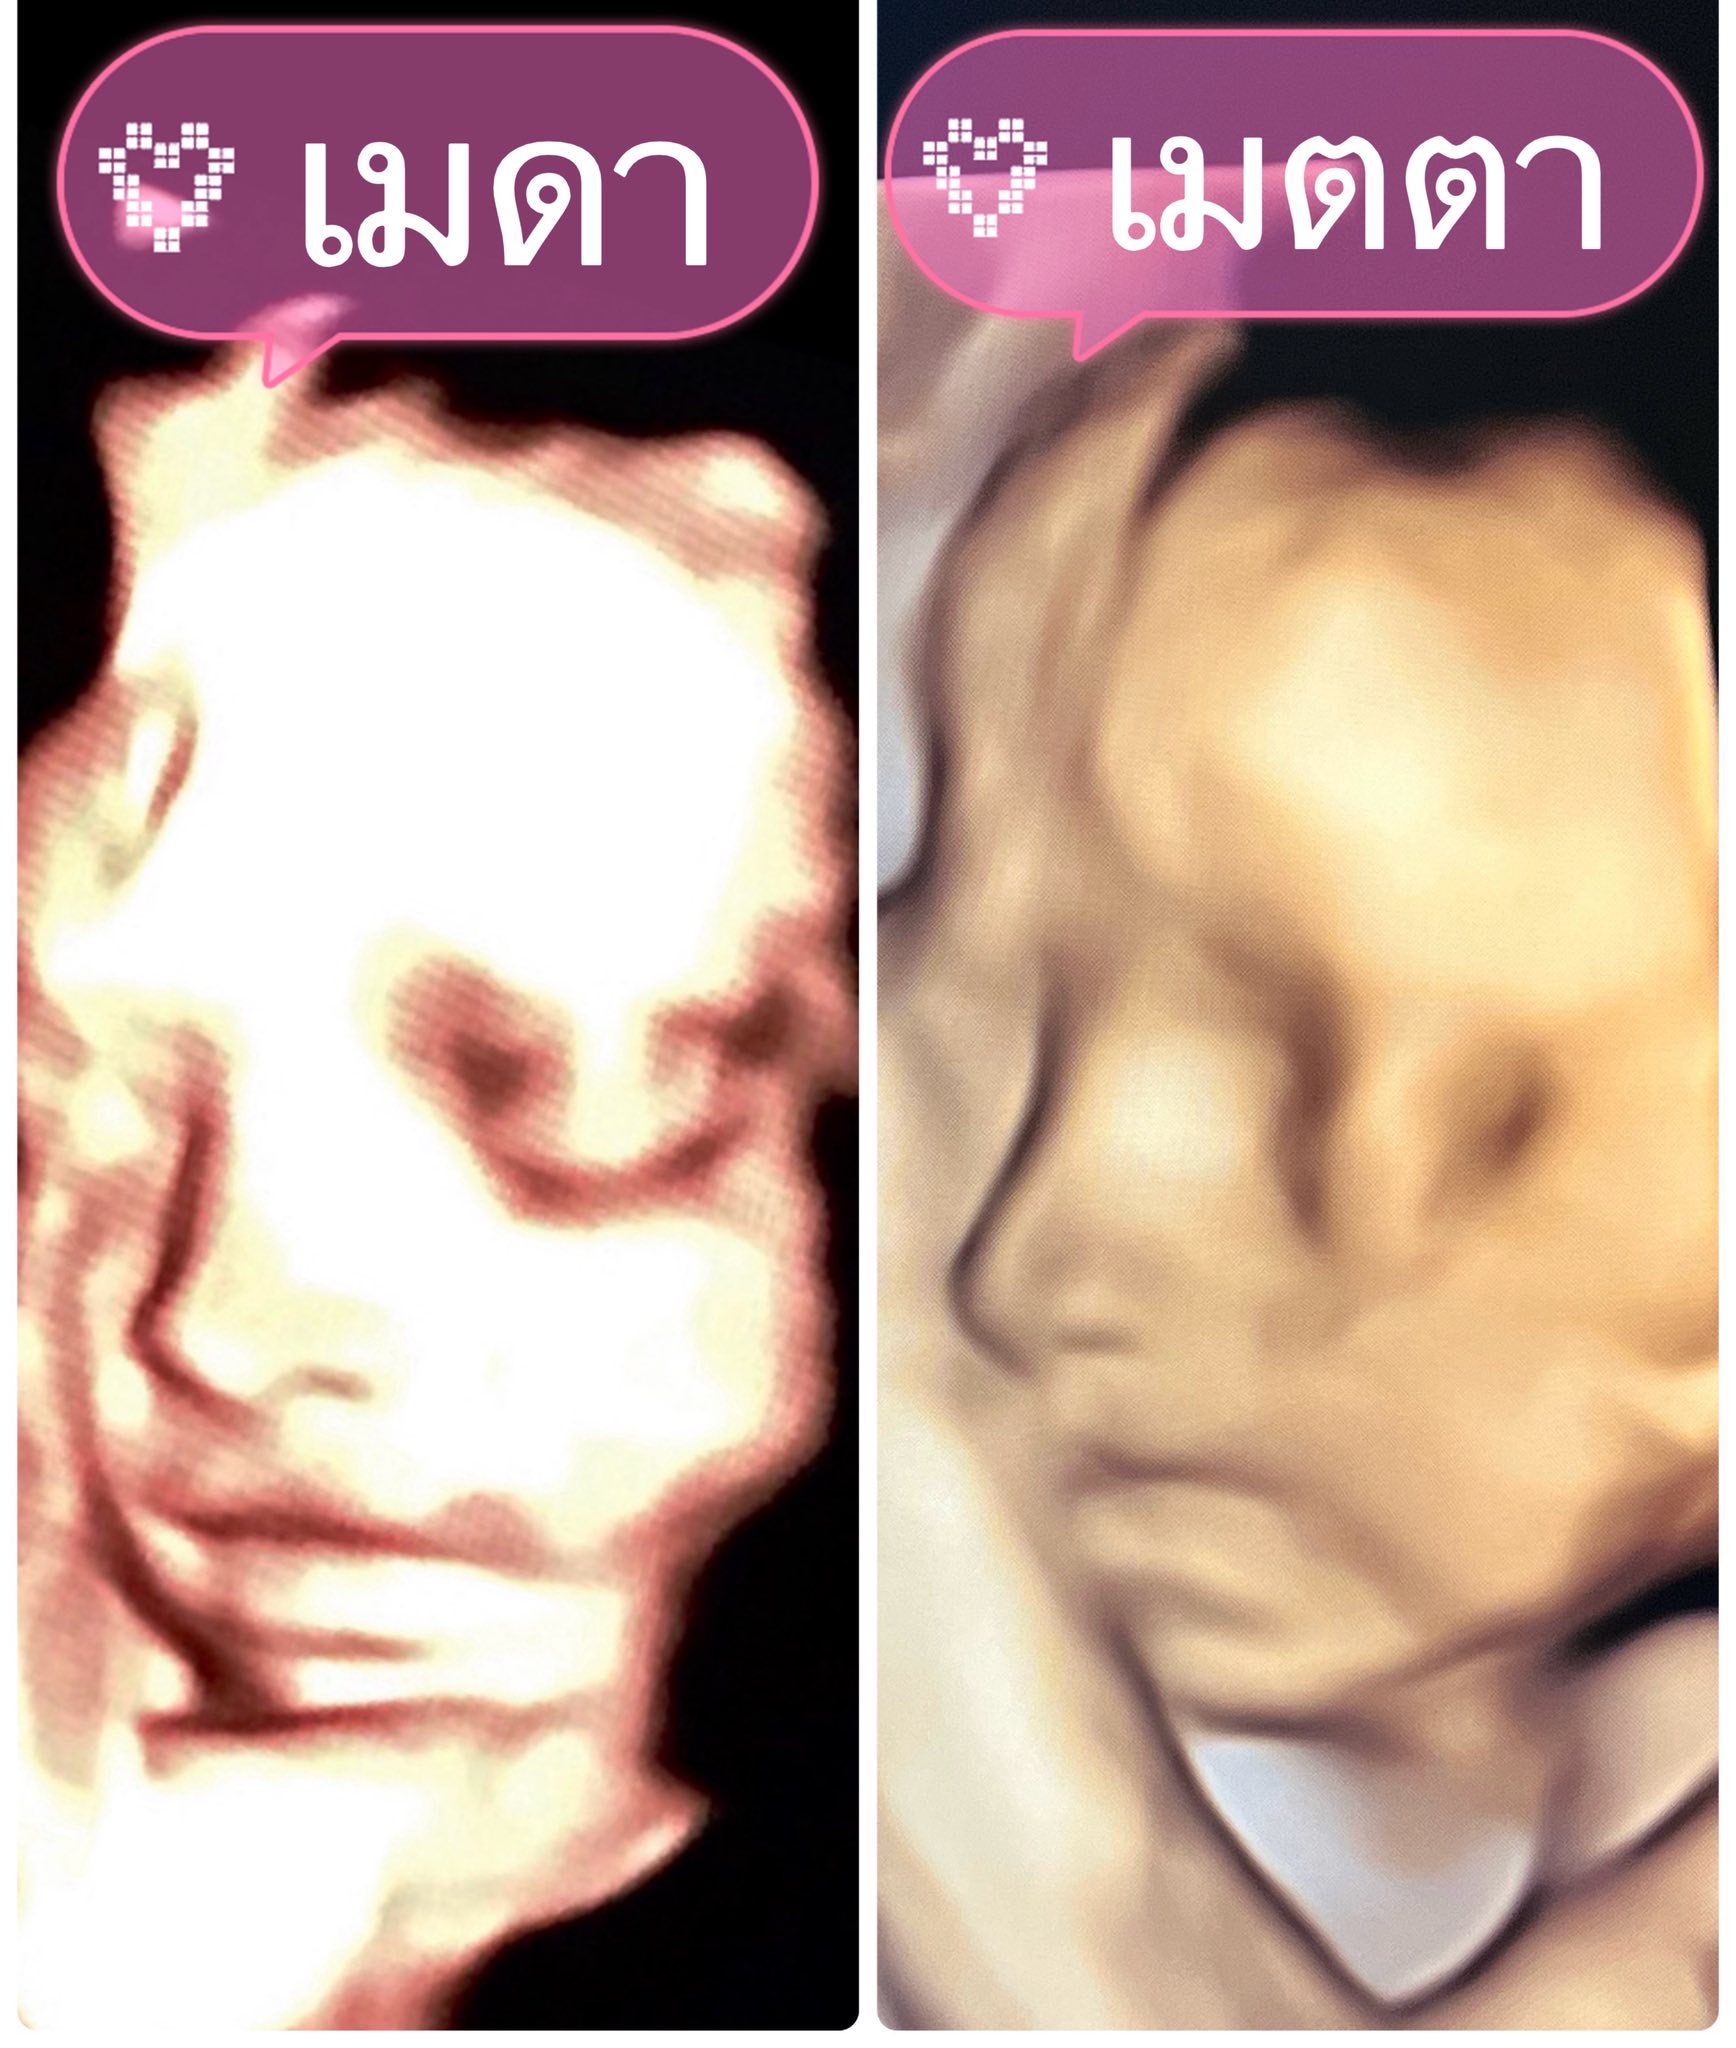

ด้าน “เจมส์ เรืองศักดิ์” ทำหน้าที่ดูแลภรรยาและลูกน้อยในครรภ์ไม่ห่าง พร้อมโพสต์ข้อความผ่านโซเซียลมีเดียว่าอบ “องครักษ์พิทักษ์คนท้อง” และ “ช่วงเวลาอันแสนพิเศษของครอบครัวเรา” ควบคู่กับภาพอัลตราซาวด์ที่เผยให้เห็นความละม้ายคล้ายคลึงของลูกสาวทั้งสองคน “น้องเมดา” และ “น้องมีเมตตา” สร้างรอยยิ้มและความประทับใจให้กับผู้ติดตามจำนวนมาก

นอกจากนี้ครูก้อยยังอัปเดตภาพอัลตราซาวด์ “น้องมีเมตตา” อายุครรภ์ 26 สัปดาห์ แบบอารมณ์ดีว่า ลูกสาวชอบเอามือบังหน้า ทำให้เห็นไม่ชัดสักที แต่แอบเห็นมุมข้างหน้าเรียว ๆ น้ำหนักตอนนี้กว่า 800 กรัม อยู่ในเกณฑ์มาตรฐาน ขณะที่น้ำหนักคุณแม่อยู่ที่ 69 กิโลกรัม และยังเพิ่มตามเกณฑ์เหมาะสม